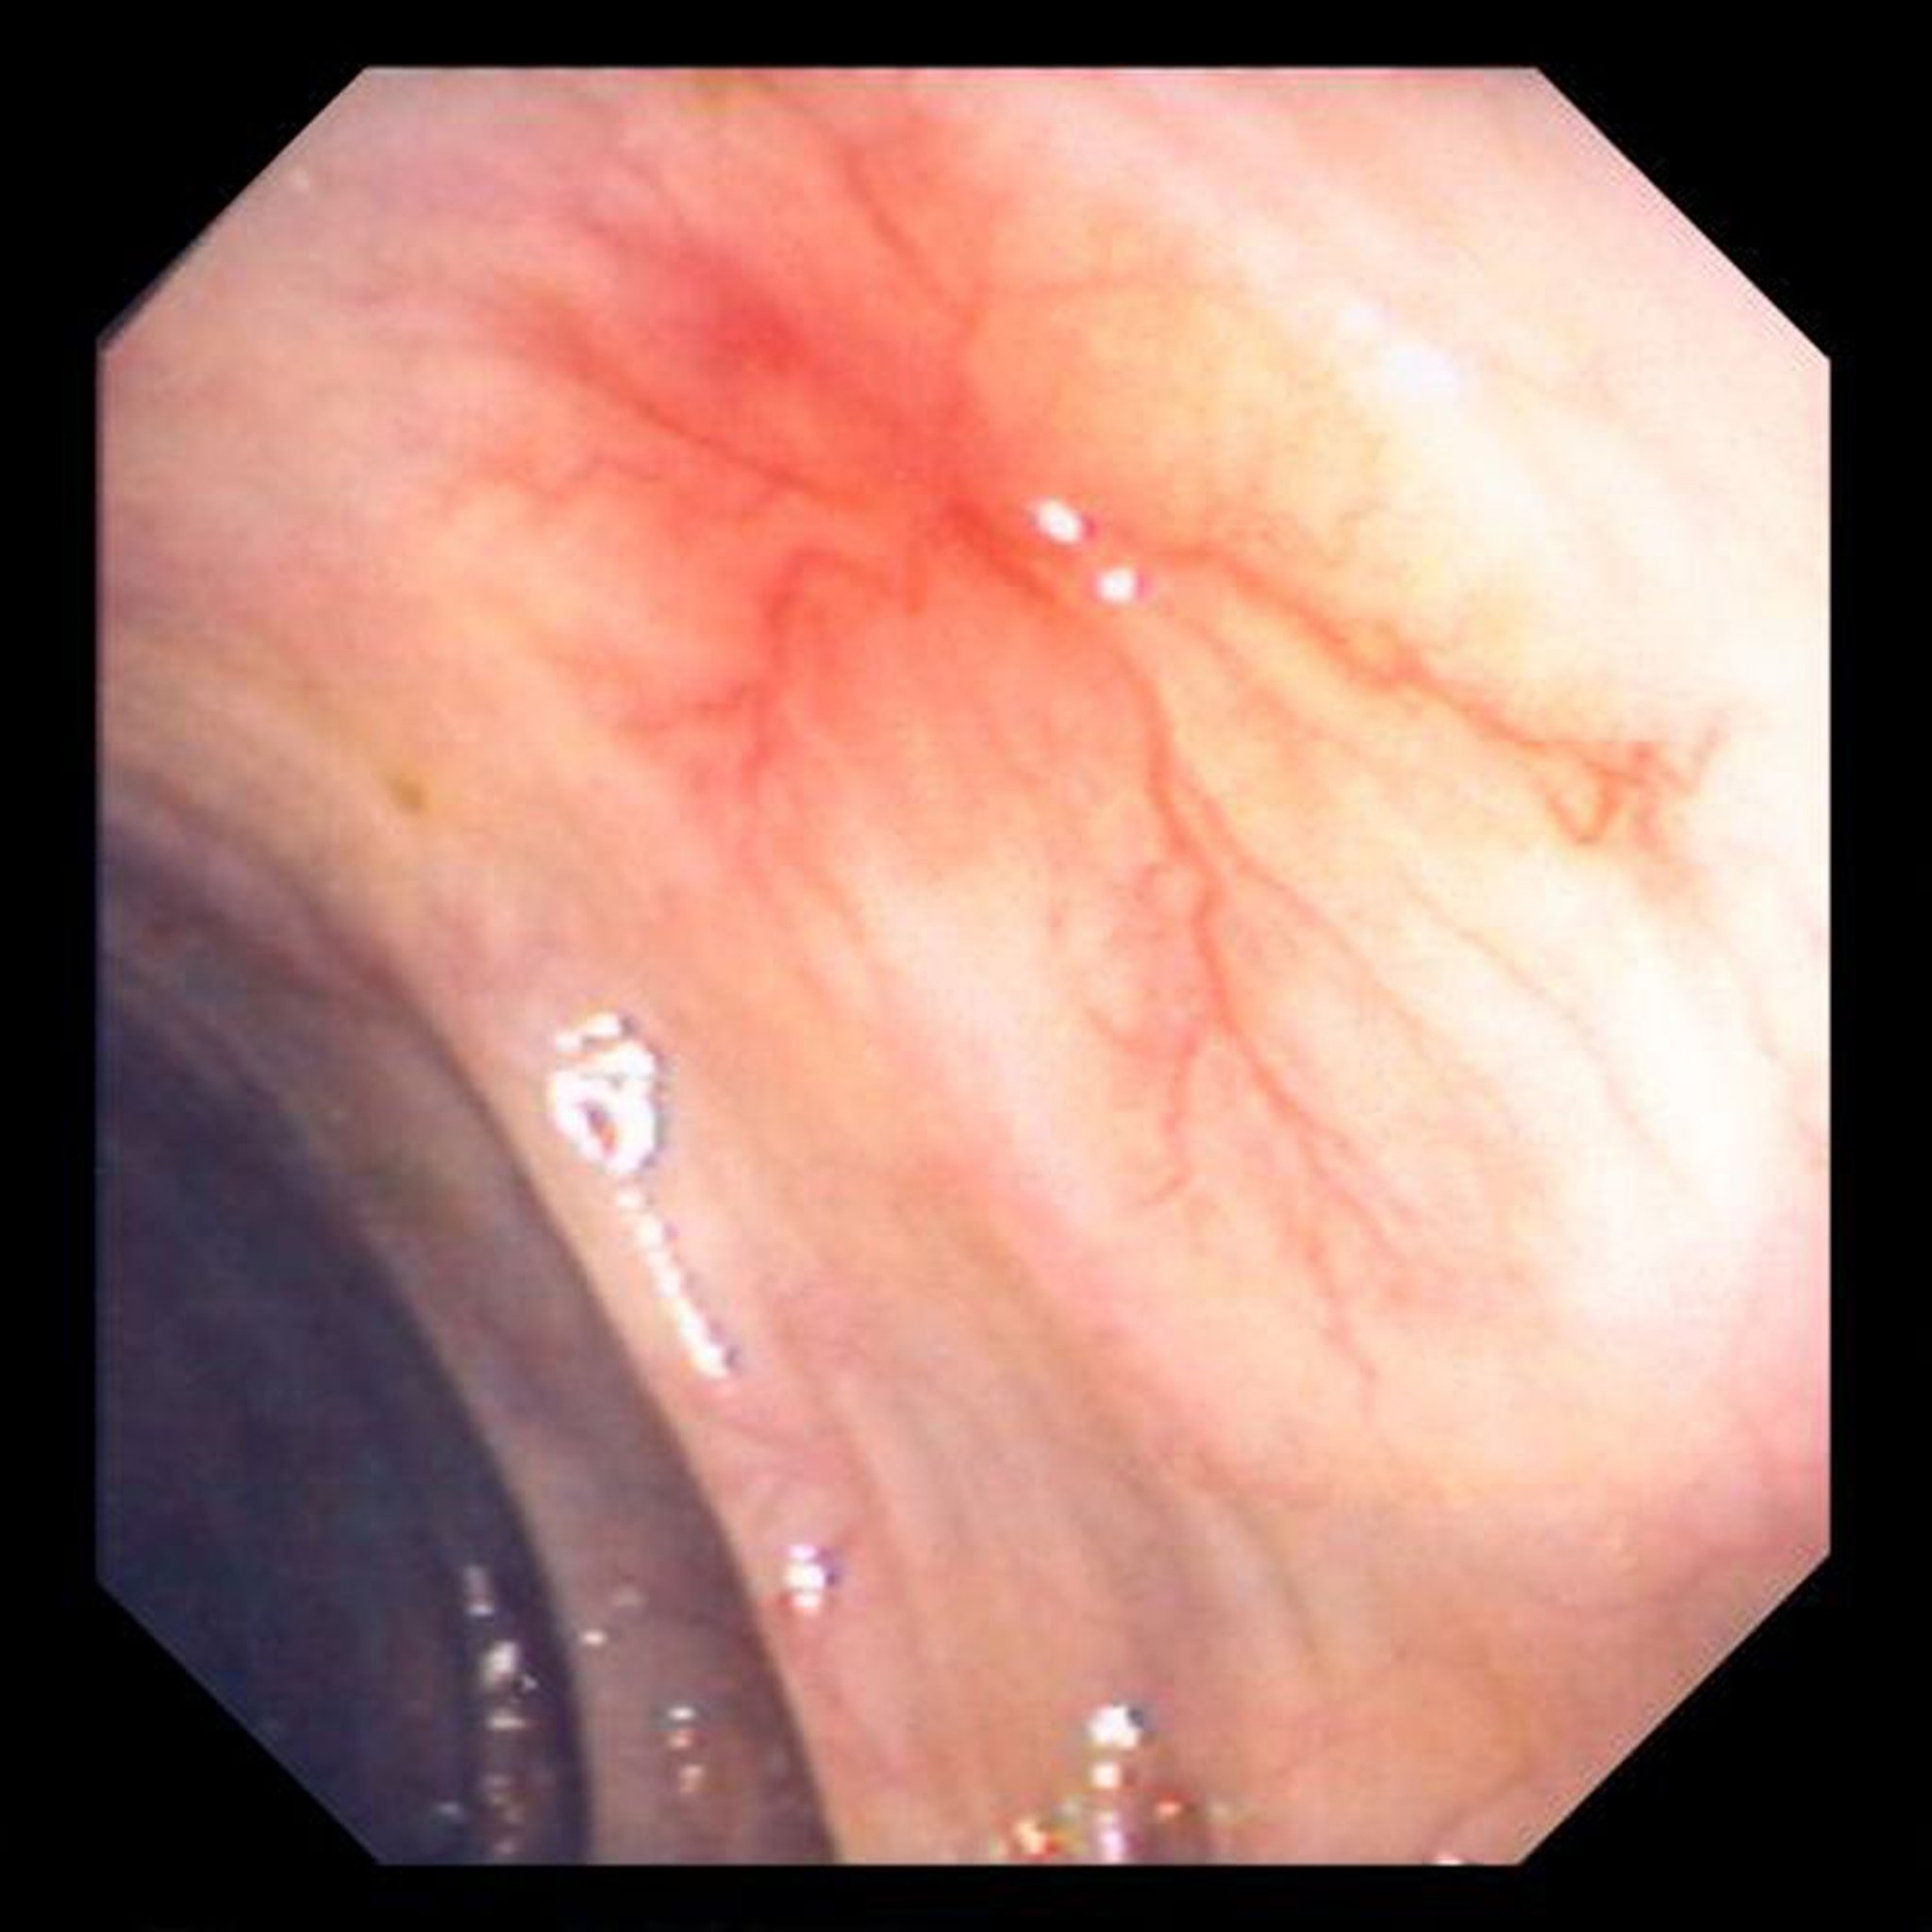

Аномальные изменения кровеносных сосудов (ангиодисплазия) в кишечнике

На этой фотографии показан аномальный кровеносный сосуд стенки кишечника.

Изображение предоставлено д-ром Дэвидом М. Мартином (David M. Martin, MD).